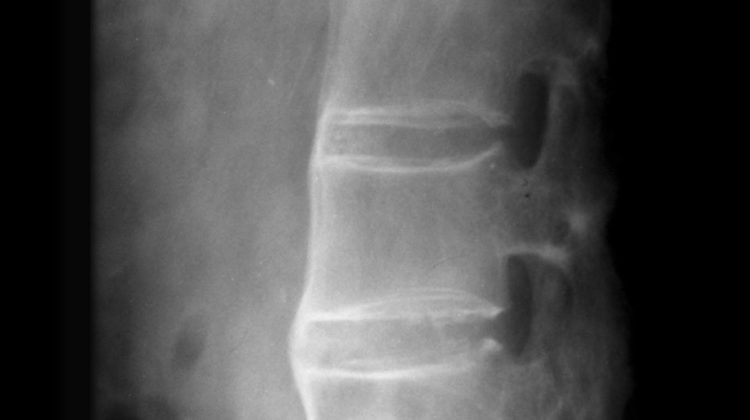

Ankylosing spondylitis is a type of arthritis that affects mainly the spine, pelvis, and ribs. It chiefly affects young males and eventually causes abnormal stiffening and immobility of the involved joints. It is an inflammatory disease that has no known specific cause yet although genetic factors have been shown to play a role. Treatment involves symptomatic relief of pain and … [Read more...]